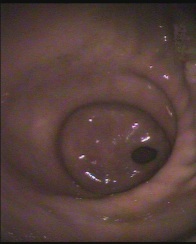

Magenausgang (Pylorus = Pförtner)